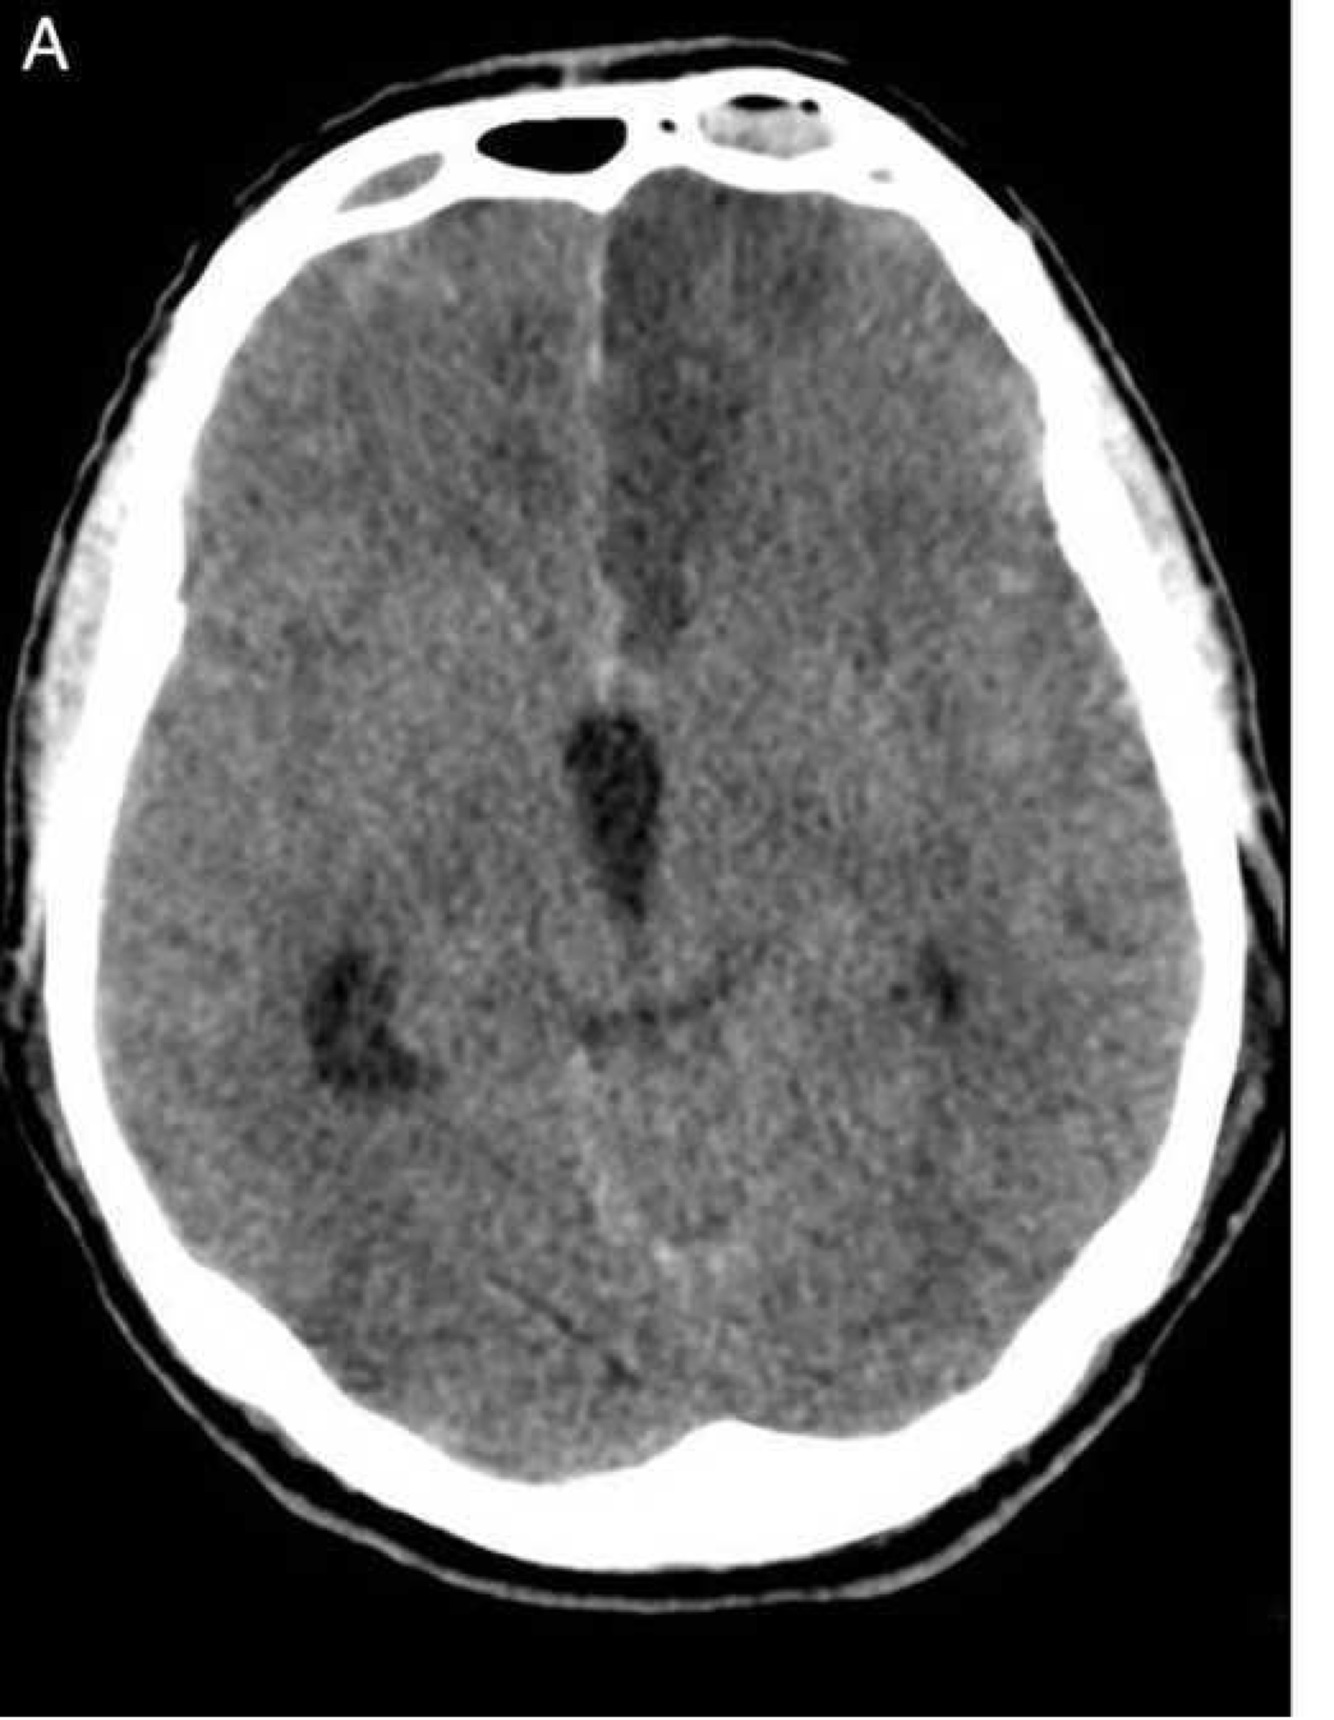

Estudio de imagen solicitado para hidrocefalia

A

TC